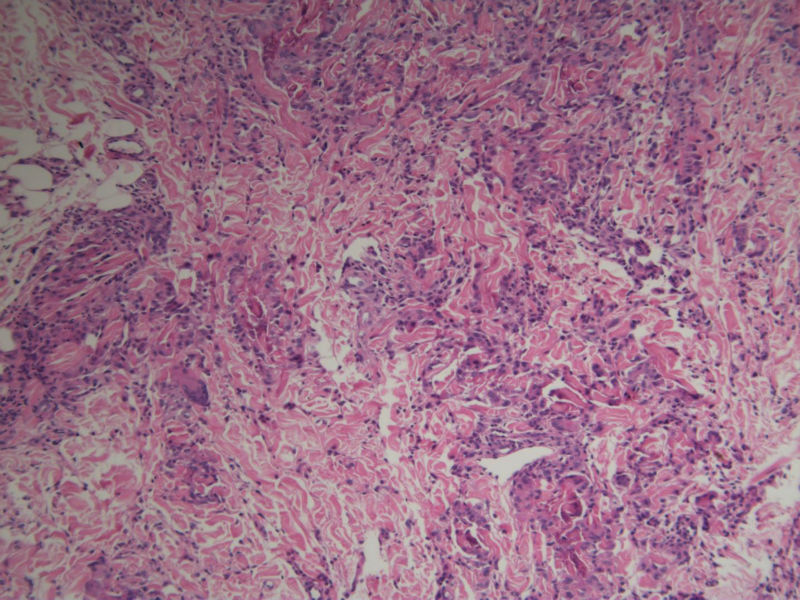

患者 男,8岁,双小腿渐粗红肿伴痒20余天,皮疹渐扩大,且出现硬化萎缩,入院后发现肺吸虫(+)。临床考虑:肺吸虫病硬皮病。请问斑竹大人考虑啥?

肺吸虫引起的嗜酸性粒细胞增多性疾病

肉芽肿性病变。肺吸虫能继发硬皮病吗?

肉芽肿中央不是凝固性坏死,好像是胶原纤维,否为环状肉芽肿或类脂质渐进性坏死

要考虑Wells综合征,依据有肺吸虫检查阳性、皮疹表现为肉芽肿样表现,可见到火焰征,不知道临床上血液分析检查结果如何,以及其他的检查结果怎么样?

但镜下没看见嗜酸性粒细胞呀

肺吸虫皮下结节表现为肉芽肿炎症,这里的图片所显示的就是真皮及皮下组织的肉芽肿炎症,若是肺吸虫所致,按理是多少能见到嗜酸粒细胞的,但这里确实是没有看到,也没见可以的虫体征象,是没切到?也似乎没见很明显的硬皮病相关表现。

但是结合病史,患儿的皮肤改变可能还是用跟肺吸虫有关的东西来解释为妥?

补充(临床医生邮件提供)该病人是一个8岁的小男孩,此次就诊主因双小腿肿胀发硬伴痒20天入院。既往体健,无内脏疾病史,入院时无发热、咳嗽、咳痰,无腹痛、腹泻等不适。专科检查:双小腿弥漫肿胀性褐色斑块,皮疹边界清楚,左小腿较右小腿肿胀明显,左小腿皮肤弹性较正常差,皮温正常,皮肤表面未见抓痕,未见红斑、丘疹、结节等,未见糜烂、破溃。入院查血分析嗜酸性粒细胞百分之六十多,余未见明显异常;体液免疫是IgE升高明显,有一百多倍吧,具体记不清。行肺吸虫皮试阳性,胸部CT及全腹CT检查均可见感染性病变,颅脑CT未见异常。给予杀虫治疗1疗程后,左小腿肿胀明显消退,现两小腿粗细相当,左小腿肿胀发硬也明显缓解,但褐色色沉一直未见明显消退,而且还向大腿蔓延,未见明显肿胀发硬的改变。患者现无瘙痒、肿胀感等不适。患者皮疹并不是肺吸虫病的典型皮疹,故行病理检查明确皮疹是否于肺吸虫病相关。

谢谢!开了眼界了!再次细看病理图,那些类似于“火焰征”的还真是像脱颗粒的嗜酸粒细胞,只是显而易见的嗜酸粒细胞不多见。末梢血嗜酸粒细胞那么多···推想皮疹应该是和肺吸虫有关,只是我们这辈的没啥见过、也很难见到了,还请前辈多多指点啊!

1、患者的皮损与血液中嗜酸性粒细胞增多有关,病理改变的确类似Wells综合征的灶状坏死,但没有特异性。

2、嗜酸性粒细胞增多可以表现为毛囊炎,蜂窝织炎,脂膜炎,筋膜炎,嗜酸性皮病和增多综合征等,

3、其产生的原因常常是寄生虫,此例明确有肺吸虫。所以两者有明确的相关性。